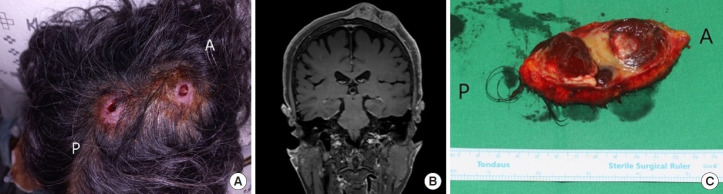

The incidence of anaplastic large cell lymphoma is 0.25 cases per 100,000 people. It usually causes lymphadenopathy and B symptoms; however, diverse cutaneous manifestations can also be observed. We report a rare case of anaplastic large cell lymphoma of the scalp, which presented similarly to a ruptured epidermal cyst. A 77-year-old woman visited the outpatient clinic complaining of scalp masses that had appeared 2 months before. One week before her visit, she had undergone incision and drainage at a local clinic but showed no improvement. Before surgery, facial magnetic resonance imaging revealed two suspicious ruptured cystic masses. Surgical excision was performed with a 1-cm free margin from the soft mass. Histopathology confirmed anaplastic lymphoma kinase-negative anaplastic large cell lymphoma. After wide excision and skin grafting for wound reconstruction, followed by consultation with a hemato-oncologist and radiation oncologist, chemotherapy was planned to prevent recurrence. Differentiating anaplastic lymphoma kinase-negative anaplastic large cell lymphoma of the scalp from a ruptured epidermal cyst-like mass proved challenging. We recommend considering the possibility of anaplastic large cell lymphoma if an epidermal cyst-like mass does not respond to antibiotics or conventional dressing, as illustrated by our rare case.